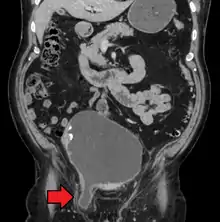

.jpg.webp)

An indirect inguinal hernia results from the failure of embryonic closure of the deep inguinal ring. In the male it can occur after the testicle has passed through the deep inguinal ring. It is the most common cause of groin hernia. A double indirect inguinal hernia has two sacs.